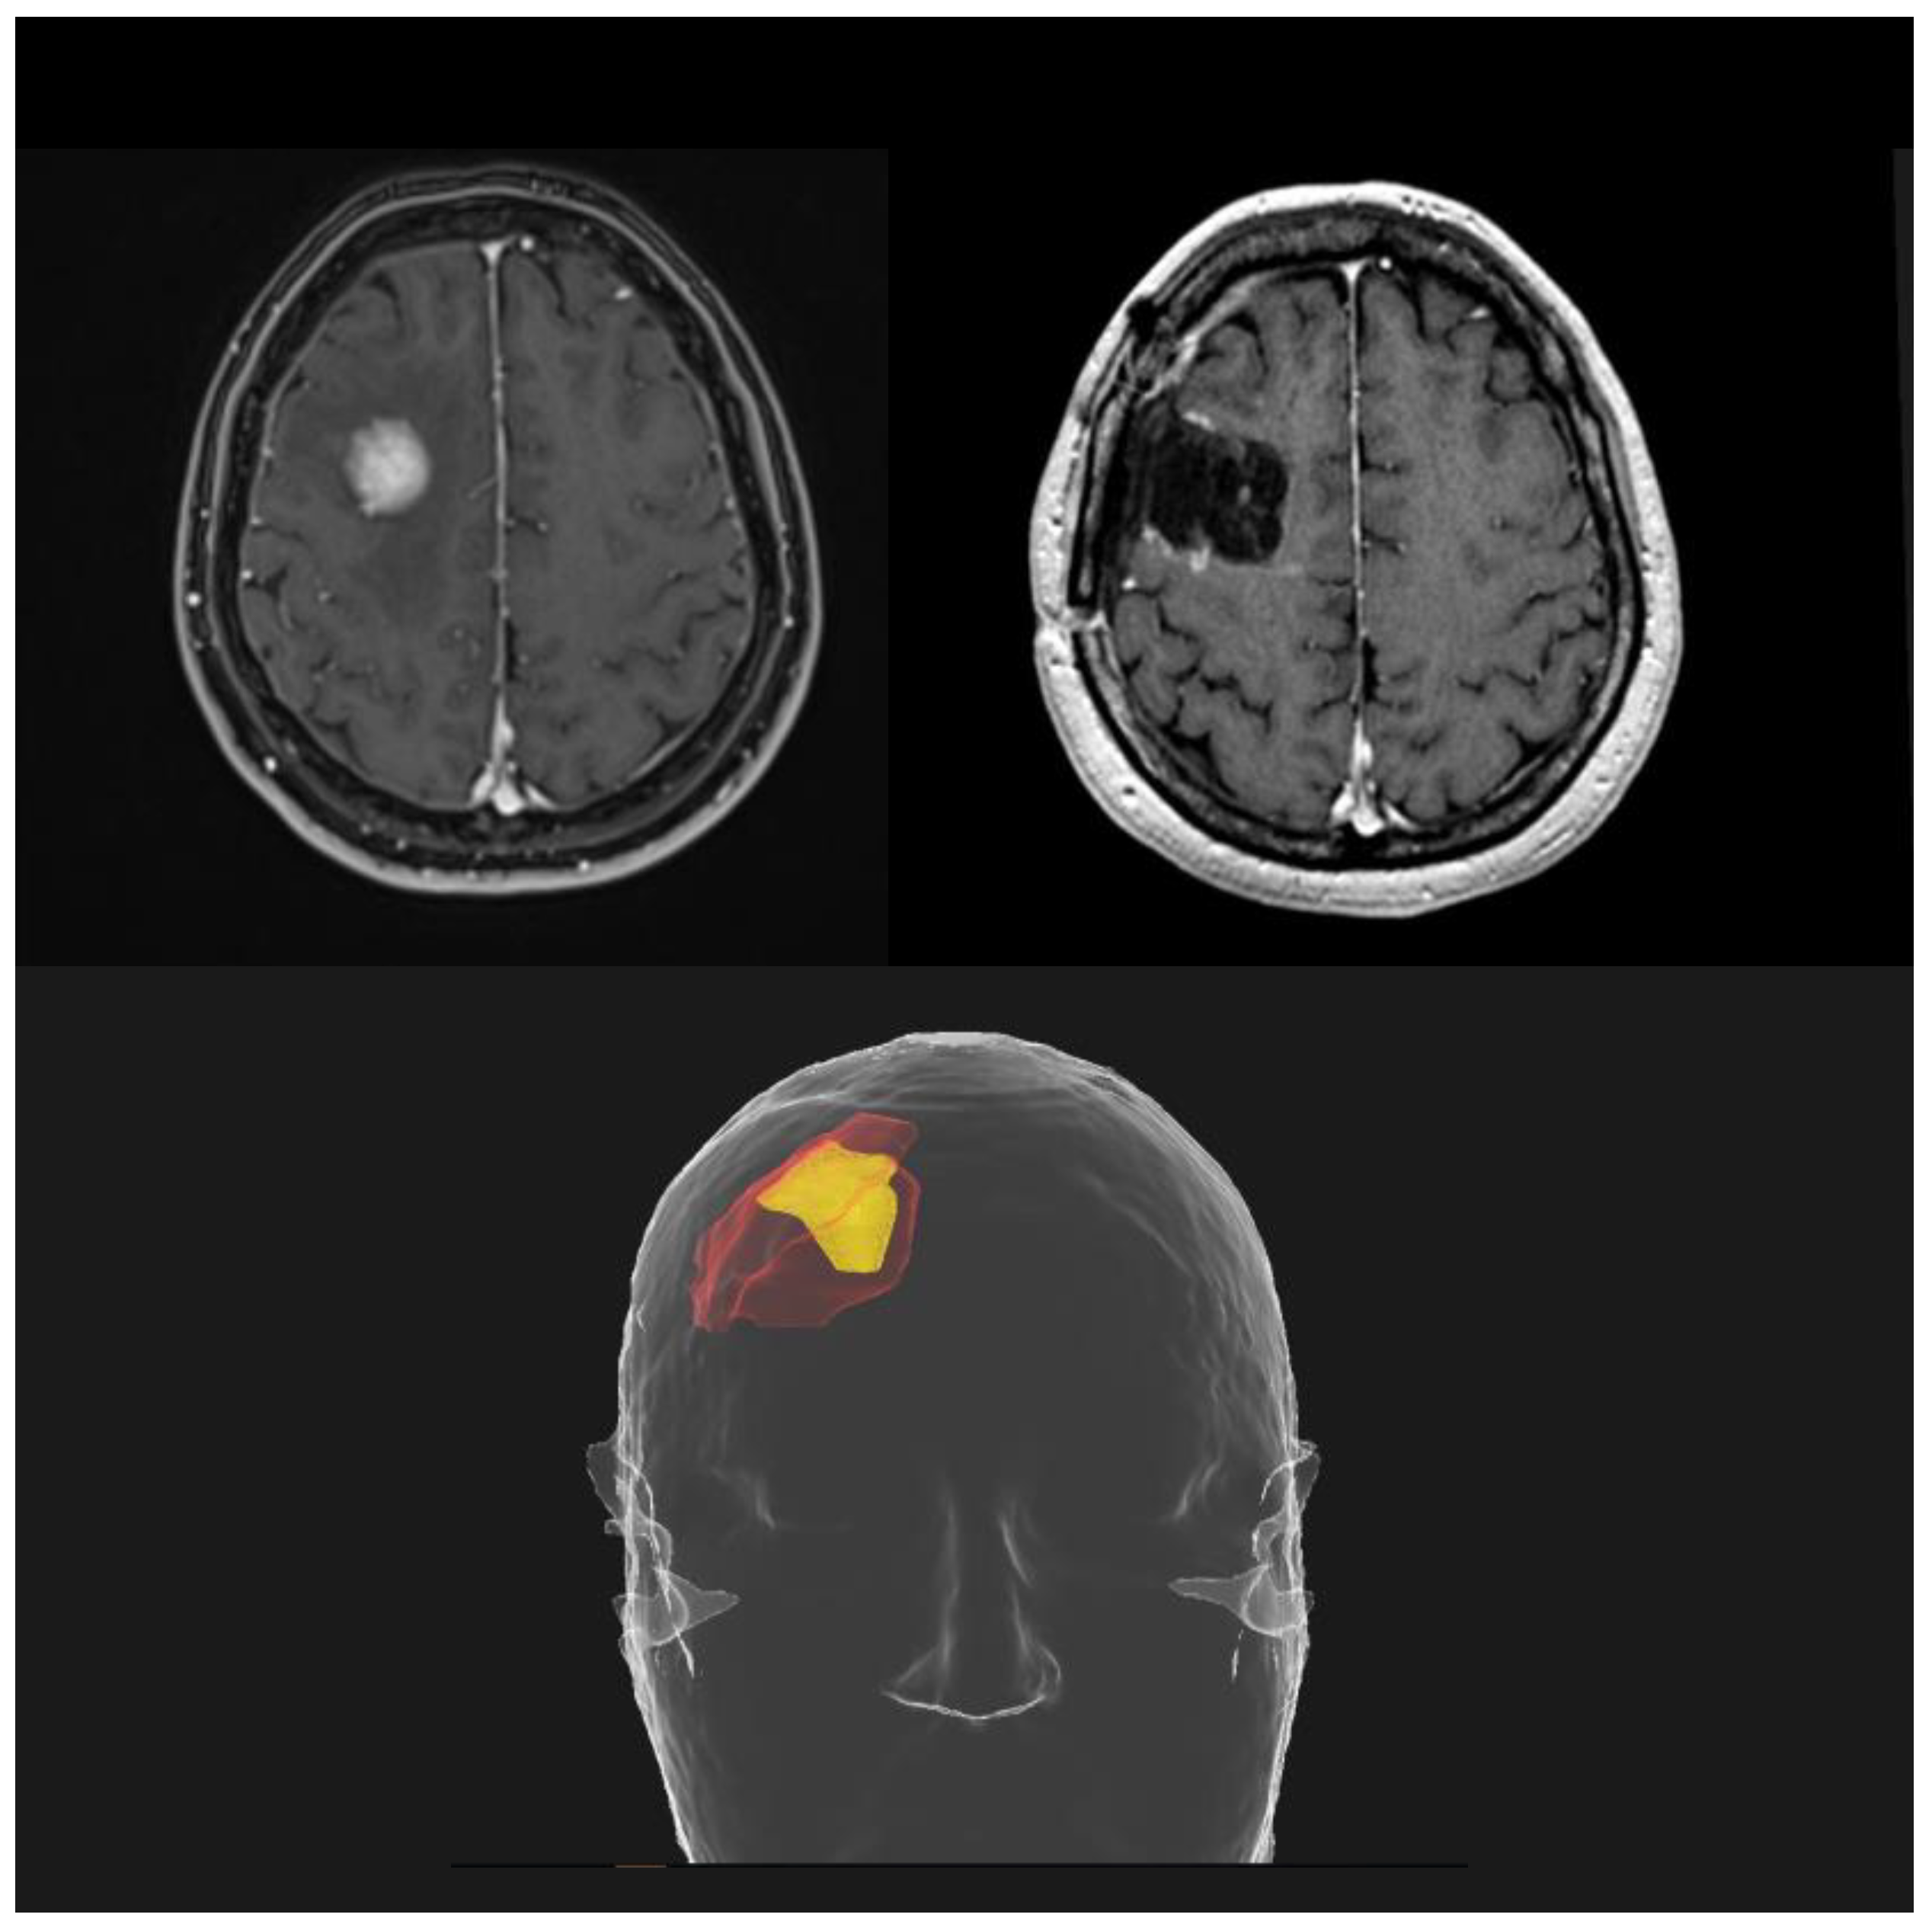

- Rajkumar, S.; Liang, Y.; Wegner, R.E.; Shepard, M.J. Utilization of Neoadjuvant Stereotactic Radiosurgery for the Treatment of Brain Metastases Requiring Surgical Resection: A Topic Review. J. Neurooncol. 2022, 160, 691–705. [Google Scholar] [CrossRef] [PubMed]

- Asher, A.L.; Burri, S.H.; Wiggins, W.F.; Kelly, R.P.; Boltes, M.O.; Mehrlich, M.; Norton, H.J.; Fraser, R.W. A New Treatment Paradigm: Neoadjuvant Radiosurgery Before Surgical Resection of Brain Metastases With Analysis of Local Tumor Recurrence. Int. J. Radiat. Oncol. Biol. Phys. 2014, 88, 899–906. [Google Scholar] [CrossRef] [PubMed]

- Patel, K.R.; Burri, S.H.; Asher, A.L.; Crocker, I.R.; Fraser, R.W.; Zhang, C.; Chen, Z.; Kandula, S.; Zhong, J.; Press, R.H.; et al. Comparing Preoperative With Postoperative Stereotactic Radiosurgery for Resectable Brain Metastases: A Multi-Institutional Analysis. Neurosurgery 2016, 79, 279–285. [Google Scholar] [CrossRef]